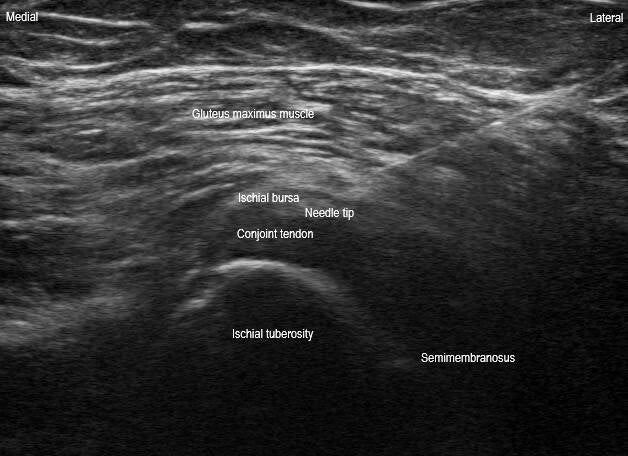

This is a transverse plane image short axis to the proximal hamstring origin at the ischial tuberosity during an ischial bursa injection. The needle can be seen in a posterolateral to anteromedial in-plane orientation with the needle tip in the ischial bursa (plane between the hamstring and gluteus maximus). The injectate should flow peritendinously.